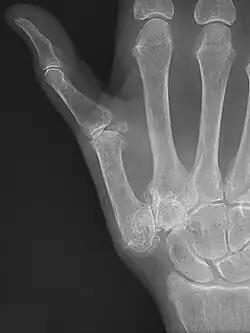

Trapeziometacarpal osteoarthritis (TMC OA) is, also known as osteoarthritis at the base of the thumb, thumb carpometacarpal osteoarthritis, basilar (or basal) joint arthritis, or as rhizarthrosis.[3][1][2] This joint is formed by the trapezium bone of the wrist and the metacarpal bone of the thumb. This is one of the joints where most humans develop osteoarthritis with age.[4] Osteoarthritis is age-related loss of the smooth surface of the bone where it moves against another bone (cartilage of the joint).[3][5] In reaction to the loss of cartilage, the bones thicken at the joint surface, resulting in subchondral sclerosis. Also, bony outgrowths, called osteophytes (also known as "bone spurs"), are formed at the joint margins.[6]

TMC OA is diagnosed based on symptoms and signs.[8] Radiographs can confirm the diagnosis and the severity of TMC OA. Other diagnoses in this region include scaphotrapezial trapezoid arthritis and first dorsal compartment tendinopathy (De Quervain syndrome) although these are usually easy to distinguish.

TMC OA severity was classified by Eaton and Littler which can be simplified as follows:[21][22]

Stage 1:

- slight widening of the joint space

- < 1/3 subluxation of the joint (in any projection)

Stage 2:

- Osteophytes, < 2 mm in diameter, are present. (usually adjacent to the volar or dorsal facets of the trapezium)

Stage 3:

- Osteophytes, > 2 mm in diameter, are present (usually adjacent to the volar and dorsal facets of the trapezium)

- Slight joint space narrowing

Stage 4:

- Narrow joint space

- Concomitant scaphotrapezial arthritis